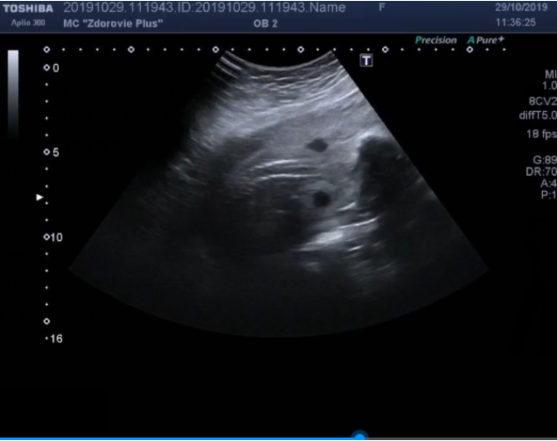

整个过程,时常会收到大冷总来自莫斯科发来的产检报告,还有3D的B超照片和视频,看着那个一点点成型,直到能看清五官的小人儿,其实那个时候就感觉心已经化了。

上面我宝宝的B超图,每天闲下来的时候,我就会打开莫斯科发来的宝宝的B超视频,感觉我的宝宝和我一起呼吸,再多的疲累也会一扫而光。